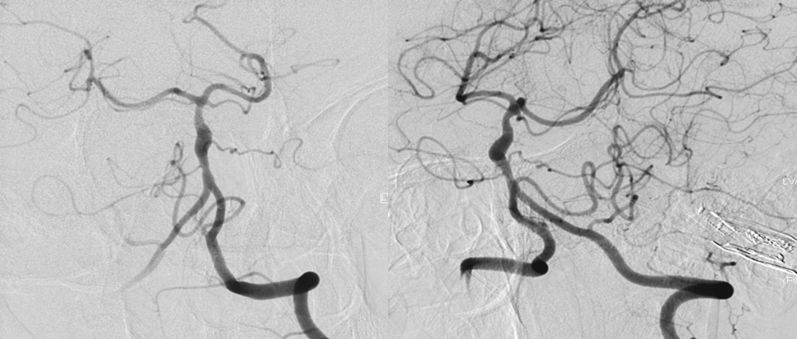

2、调整至合适的工作角度后,撤出5F中间导管,将5F Navien 通过6F长鞘置入左侧V3段。路图引导下由2 m Synchro-14微导丝将T-track支架微导管超选进左侧大脑后动脉P2段(图9)。

图9

3、多个投射角度辅助下,将一枚3x35 mm的Tubridge支架经T-track支架微导管缓慢释放(图10)。

图10